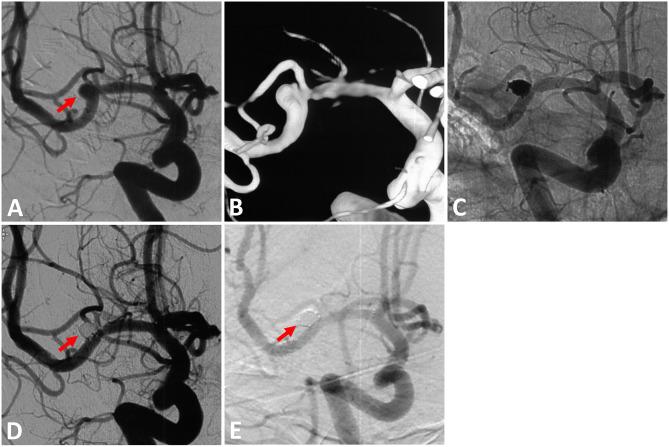

Stenting in ruptured middle cerebral artery (MCA) aneurysms was reported with a high perioperative complication rate. However, the treatment devices and physician's experience have continued to evolve. We performed this retrospective study to evaluate the safety and efficacy of LVIS stent-assisted coiling for ruptured MCA aneurysms. Patients with acutely ruptured MCA aneurysms treated between November 2014 and October 2019 were retrospectively reviewed. Clinical and angiographic data of those treated with LVIS stents were collected from a prospectively maintained database. A total of 40 patients with 40 ruptured MCA aneurysms were enrolled, which comprised 26.3% (40/152) of all the ruptured MCA aneurysms at the same time. All stents were successfully deployed except for one (2.5%), which had a poor stent opening. Ischemic procedure-related complications were encountered in three patients (7.5%). One patient died of complications related to high-grade SAH on admission. Follow-up (mean 15.9 months) angiography was performed for 36 patients, which showed 33 (91.7%) aneurysms were completely occluded, 1 (2.8%) was improved, 1 (2.8%) was stable, and 1 (2.8%) was recanalized. Clinical follow-up (mean 29.6 months) was available for all survived patients, which showed 38 (95.0%) patients had favorable neurologic outcomes (mRS score 0-2), and 2 (5.0%) patients had poor neurologic outcomes. The use of LVIS stents is feasible, safe, and effective with glycoprotein IIb/IIIa inhibitor for the treatment of ruptured MCA aneurysms in the acute setting. Prospective, multicenter studies with larger sample sizes are still required to further evaluate the safety and long-term efficacy.

据报道,大脑中动脉(MCA)破裂动脉瘤的支架置入术围手术期并发症发生率较高。然而,治疗设备和医生的经验一直在不断发展。我们进行了这项回顾性研究,以评估LVIS支架辅助弹簧圈栓塞术治疗破裂MCA动脉瘤的安全性和有效性。对2014年11月至2019年10月期间接受急性破裂MCA动脉瘤治疗的患者进行了回顾性分析。从一个前瞻性维护的数据库中收集了接受LVIS支架治疗患者的临床和血管造影数据。共纳入40例患有40个破裂MCA动脉瘤的患者,占同期所有破裂MCA动脉瘤的26.3%(40/152)。除1例(2.5%)支架展开不佳外,所有支架均成功置入。3例患者(7.5%)出现与缺血相关的手术并发症。1例患者因入院时与高级别蛛网膜下腔出血相关的并发症死亡。对36例患者进行了随访(平均15.9个月)血管造影,结果显示33个(91.7%)动脉瘤完全闭塞,1个(2.8%)有所改善,1个(2.8%)稳定,1个(2.8%)再通。所有存活患者均进行了临床随访(平均29.6个月),结果显示38例(95.0%)患者神经功能预后良好(mRS评分0-2),2例(5.0%)患者神经功能预后较差。在急性情况下,使用LVIS支架联合糖蛋白IIb/IIIa抑制剂治疗破裂MCA动脉瘤是可行、安全且有效的。仍需要进行前瞻性、多中心、大样本量研究以进一步评估其安全性和长期疗效。